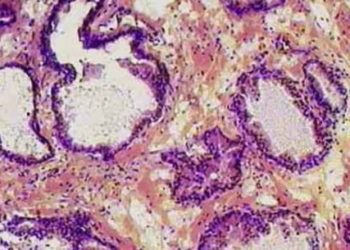

Image: PD Prostate Histology 1. Serial repeat prostate biopsies may raise the absolute risk of infectious morbidity for patients by ...